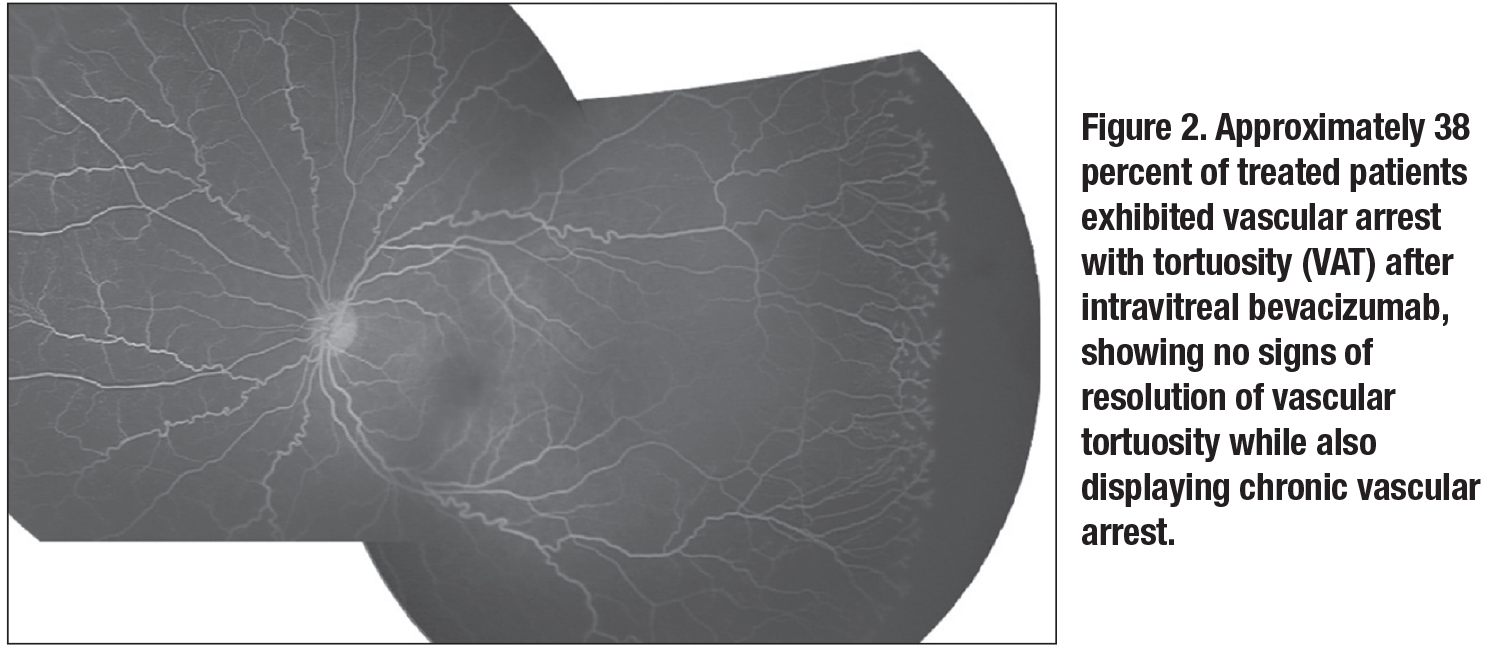

Of the eyes that did not completely vascularize (n=89), they found that 39 (43.8 percent) experienced resolution of plus disease and vascular tortuosity, but had chronic vascular arrest, termed “vascular arrest alone” (VAA, Figure 1, page 29). Thirty-four eyes (38.2 percent) didn’t experience resolution of vascular tortuosity while also displaying chronic vascular arrest, termed “vascular arrest with tortuosity” (VAT, Figure 2, page 30). Sixteen eyes (18 percent) had reactivated ROP, defined as recurrence of stage of disease; these were acutely treated with ablative laser.

Therefore, when considering all IVB treated eyes (n=92), approximately 3

percent reached full vascular maturation, 42 percent exhibited VAA, 38 percent exhibited VAT and 17 percent exhibited disease reactivation (Figure 3, page 33). This series reported no retinal progressive detachments. All patients not reaching full vascular maturation (97 percent) underwent ablative laser therapy at the time of FA (typically at around 60 weeks PMA).